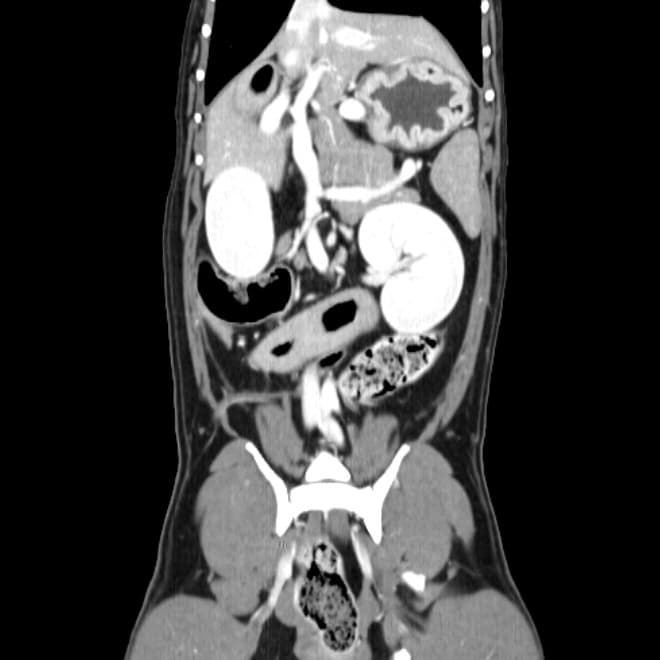

동탄 1 신도시 최초 Aquilion CX/128 slice CT를 동물병원에 도입하였습니다. 최고 사양 CT 모델 Aquilion CX/128 slice를 활용하여 0.5 mm의 얇은 128개의 단면 영상을 신속히 획득 할 수 있어 마취 시간을 단축시킬 수 있습니다. 또한, 128 슬라이스의 고화질의 CT 영상을 통해 영상 왜곡을 최소화하고 X-ray에서는 확인하기 힘든 5 mm 이하의 미세 병변도 확인이 가능하여 정확한 진단을 할 수 있습니다. 심화 진단이 필요한 경우, 조영제 인젝터를 통한 동맥기 촬영으로 종양 유래 확인, 간 질환 진단, 심혈관계 진단이 용이합니다. 저희 동탄시티동물의료센터에서는 본원 환자뿐 아니라 1차 동물 병원과의 CT 촬영 의뢰 시스템을 통해서 원활한 협진이 가능하도록 최선을 다하고 있습니다.

0164 채널 CT 촬영을 통해서 신속하게 고화질 영상을 얻어, 종양 유래 확인 및 전이 평가, 간문맥단락증(PSS), 선천적 뼈 기형과 같은 심화된 진단을 할 수 있습니다.